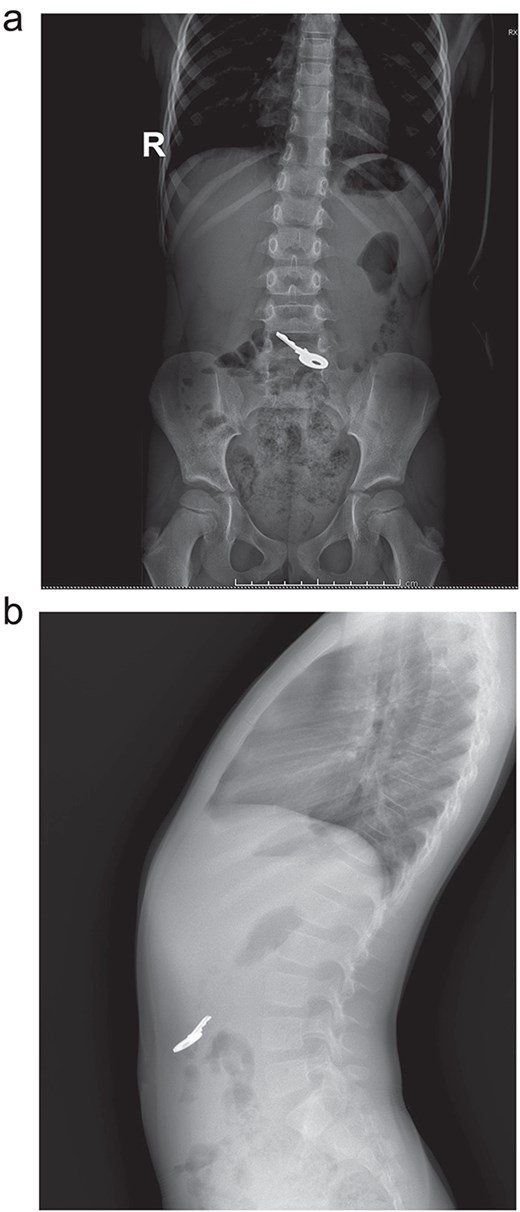

On clinical evaluation, a completely asymptomatic patient was encountered; she was extremely nervous. However, her vital signs were normal, and she had no abdominal pain or tenderness. She passed gas and had no issues with her bowel movements. Due to this, an abdominal X-ray was requested, unveiling a foreign body (small key) in her abdomen. The foreign body appeared to be in her stomach or transverse colon; nonetheless, it did not cause any signs of obstruction (Fig. 1a and b). With these findings, the patient was admitted for close monitoring due to the risk of obstruction. An endoscopy was requested. However, it was completely normal, and the key was nowhere to be found as it had already passed through the pylorus. Another abdominal X-ray was done 48 hours after admission, showing that the foreign body was moving along the intestines (Fig. 2).

(a) X-ray: A full key is seen ingested, no pneumoperitoneum or signs of obstruction. (b) X-ray: the key is seen in the intestine.